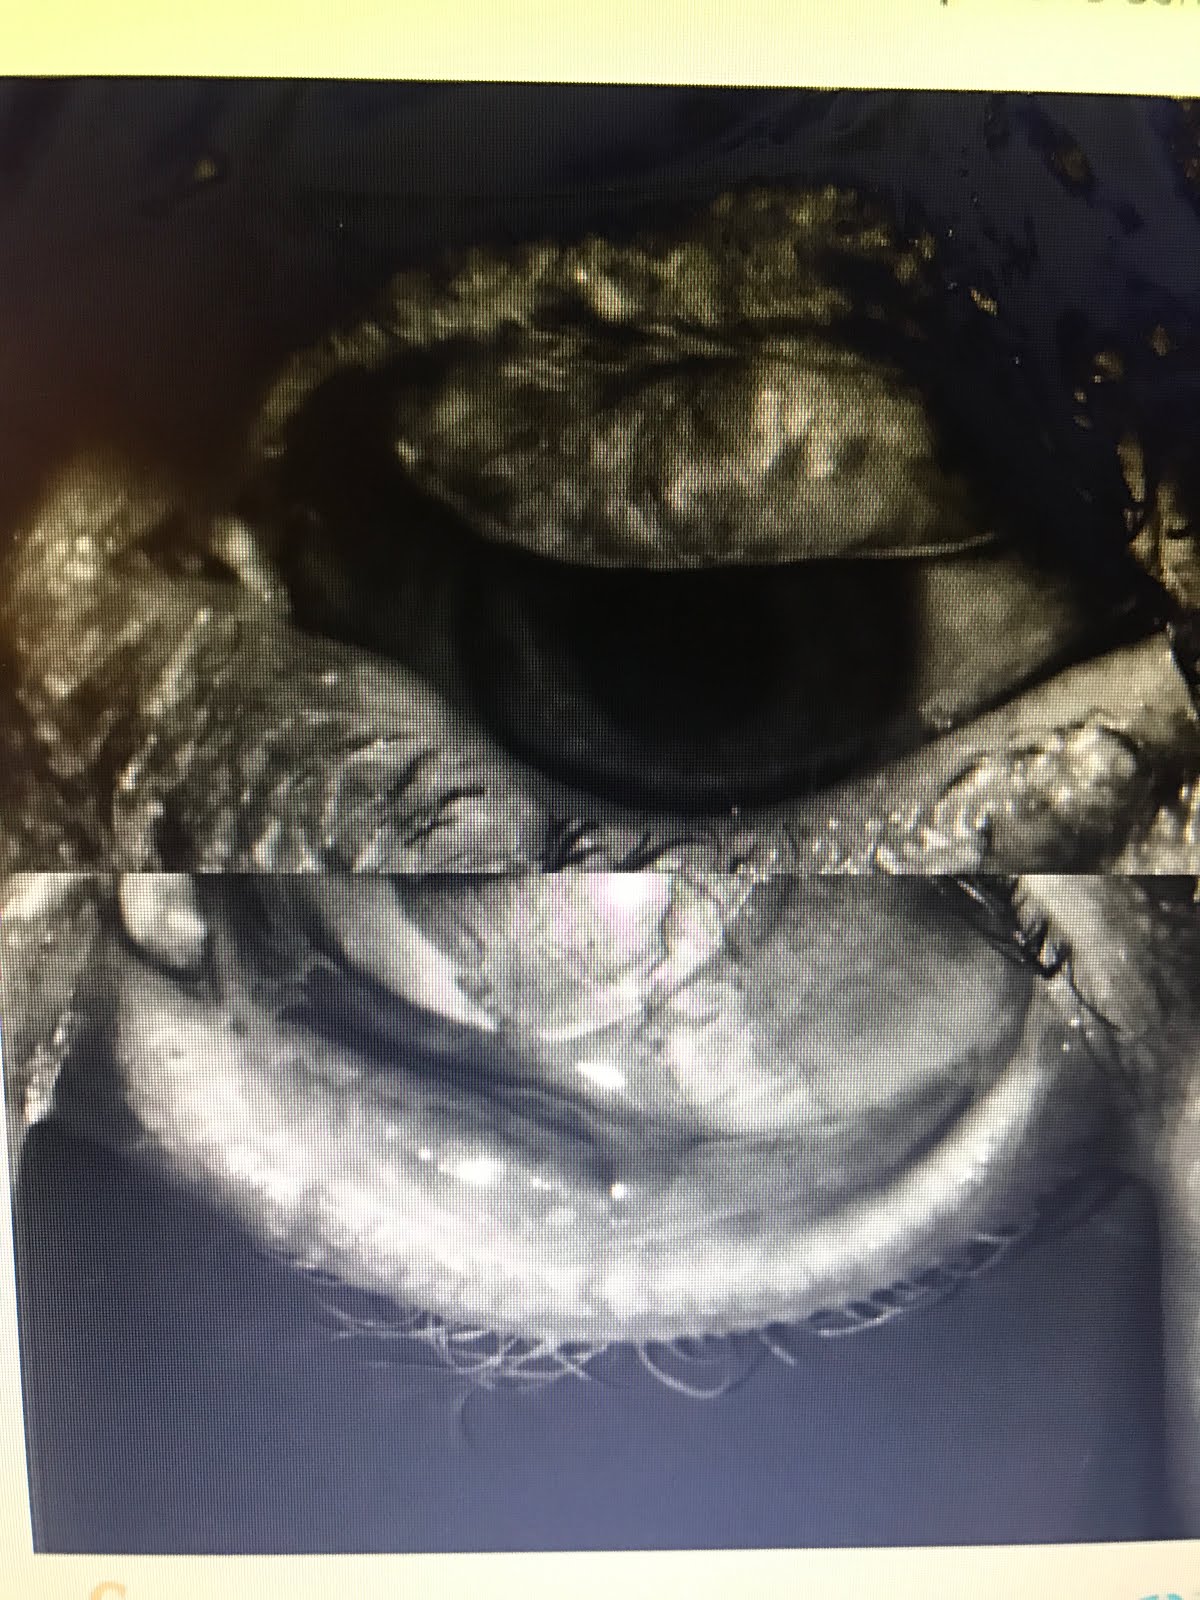

This is his Right Eye (below on left) with upper lids fipped to see Meibomian glands. This is his Left Eye (on the right side of screen). He has very few glands left.

Normal Meibomian Glands should look like “White Piano Keyes Filled with Oil” On Meibography or LipiScan or LipiView Machines seen on bottom left.

Aging, genetics, chronic blepharitis and meibomian gland dysfunction, poor diet, smoking, inflammatory issues and disease, radiation, chemotherapy, previous surgery, and I must add Chronic computer/video game/cell phone use (ie, Computer Vision Syndrome or a new term I will coin called Decreased Blinking Quality Syndrome or Decreased Blinking Rate Syndrome which can happen to even avid readers, skiers, etc) can destroy these precious glands and cause them to never function again. This loss of meibomian glands, decreases the ability of the tears to lubricate the cornea properly, which then leads to the death of the corneal epithelium, thus giving SPK. The death of the corneal epithelium, though is reversible.